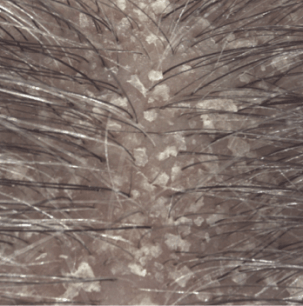

Lo shampoo KERTYOL PSO è specialmente indicato per la cura del cuoio capelluto soggetto a psoriasi.

La sua formula innovativa agisce a tutti i livelli della fisiopatologia della psoriasi. Lo shampoo trattante può essere utilizzato in associazione a trattamenti dermatologici specifici, in alternanza o come mantenimento per limitare la ricomparsa delle placche.